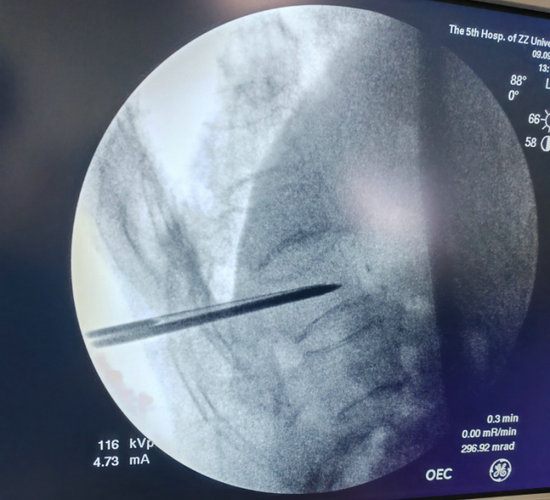

经皮穿刺椎体骨水泥成形术是一项在局麻下即可完成的手术,仅需要在背部伤椎相对应的位置切2个1cm左右的小口,然后将穿刺针穿刺到椎体前1/3的深度。

在透视确认位置良好后,即可注入骨水泥,待确认骨水泥完全凝固后,去除穿刺针,包扎伤口,手术就结束了。